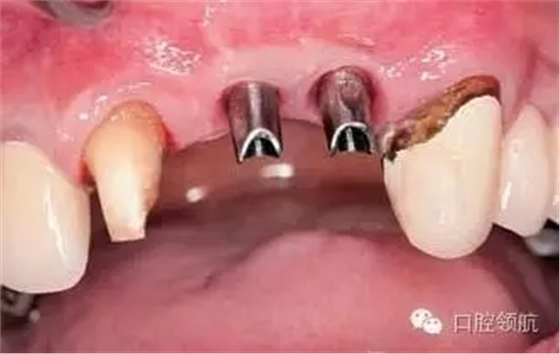

患者,53歲,男性,(右上第1、2顆牙) 缺失病例,由于牙槽骨高度不足,在行髂骨移植后進(jìn)行了種植手術(shù),但由于移植骨的吸收,種植體周?chē)难啦酃切螒B(tài)發(fā)生了變化引起了與對(duì)側(cè)同名牙的齦曲線明顯不對(duì)稱(圖1)。

圖1 去除愈合基臺(tái)后,由于移植骨的吸收,種植體周?chē)墙M織形態(tài)產(chǎn)生變化,引起與對(duì)側(cè)同名牙齦曲線明顯不對(duì)稱,作為解決的方案,提出通過(guò)外科手術(shù)再植骨和軟組織移植的方法以改善嵴頂?shù)拿缹W(xué)形態(tài)或使用修復(fù)方法來(lái)改善軟組織的美學(xué)效果。以上兩種方法供患者參考,最后患者選擇了修復(fù)的方法。